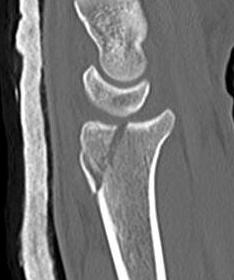

![]() |